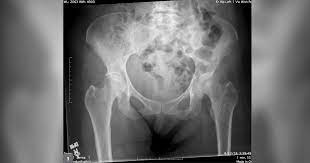

What Causes Pelvic Bone Cancer : Causes And Symptoms Of Bone Cancer - Types of biopsy procedures used to diagnose bone cancer include:. The cause of bone cancer isn't exactly known, but there are certain factors that may contribute to or increase a person's chances of forming abnormal growths in the bone. The abdomen may feel very full or heavy, and the person may also have lower back pain. Some varieties of chondrosarcoma arise from the transformation of benign cartilage lesions into cancers. Metastatic tumors of the bones are usually osteolytic, which means that they dissolve the bone and cause multiple fractures. Pelvic cancer can also occur from the spread or metastasis of other cancers from different areas of the body.

The Radiology Assistant Differential Diagnosis Of Bone Tumors from radiologyassistant.nl Osteosarcoma is probably the most common disease that is related to pelvic bone cancer, with chondrosarcoma following close behind it. The cause of bone cancer isn't exactly known, but there are certain factors that may contribute to or increase a person's chances of forming abnormal growths in the bone. Chronic pelvic pain can result from more than one condition. In contrast, some other metastatic tumors, such as those from the prostate, are commonly osteoblastic, meaning that they form new bone and increase the brittleness of the bones. Recently, doctors have recognized that some pelvic pain, particularly chronic pelvic pain, can also arise from muscles and connective tissue (ligaments) in the structures of the pelvic floor. Excluding gyn causes, ibs is the most common cause of chronic pelvic pain. Learn about the causes and risk factors for bone cancer and if there are things you can do to prevent it. And a bone that breaks.

Even though the second form of bone cancer is often not said to be pelvic bone cancer, it can still cause the same types of serious damage to the pelvis and the surrounding areas.

Chronic pelvic pain can result from more than one condition. Inserting a needle through your skin and into a tumor. Bladder, uterus, and descending colon. Suggest treatment for bone cancer. The abdomen may feel very full or heavy, and the person may also have lower back pain. Pelvic cancer can also occur from the spread or metastasis of other cancers from different areas of the body. Bone metastasis may be the first sign that you have cancer, or bone metastasis may occur years after cancer treatment. Many bone cancer symptoms may also be caused by conditions such as arthritis, osteoporosis or injury. Bone metastasis can cause pain and broken bones. Surgery to remove a tissue sample for testing. Metastatic tumors of the bones are usually osteolytic, which means that they dissolve the bone and cause multiple fractures. Your bone metastases may be: It is a rare type of cancer.

bone cancer in the hip can cause pain, limping, fractures of the bone, and hypercalcemia , a condition in which there is too much calcium in your blood. Treatments which may be considered include surgery, chemotherapy and radiotherapy. In his pelvis that spread to his bones, or they were calling it bone cancer. With rare exceptions, cancer that has spread to the bones can't be cured. There are several different types. Even though the second form of bone cancer is often not said to be pelvic bone cancer, it can still cause the same types of serious damage to the pelvis and the surrounding areas. Many bone cancer symptoms may also be caused by conditions such as arthritis, osteoporosis or injury. The abdomen may feel very full or heavy, and the person may also have lower back pain. The dna mutations that cause some inherited forms of bone cancers are known. While scientists need to carry out more research into the precise cause of bone cancer, the american cancer society state that there is a range of risk factors for bone cancer, including genetics. Cancer cells that have spread to the bone can damage the bone and cause symptoms. The most common symptom is constant pain near the bone. And a bone that breaks.